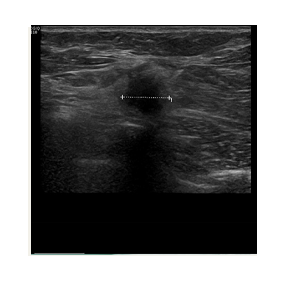

The freezing is achieved with liquid nitrogen  which flows through a probe (needle.) The needle is inserted into the tumor under ultrasound guidance. This allows us to position it very precisely, ensuring that the tumor is at the centre of the freezing zone.

This creates a large ball of ice that engulfs the tumor. By alternating freeze and thaw cycles, the cells in the tumor are destroyed. By the end of the procedure there should be no viable cancer cells left. The progress of ice ball development is closely monitored throughout the procedure to ensure safety.

Ultrasound imaging is used to locate the lesion. The breast is prepared and local anesthesia is given

Using ultrasound guidance, a visica cryoprobe is positioned in the center of the lesion

Testing – the ice ball forms around the probe